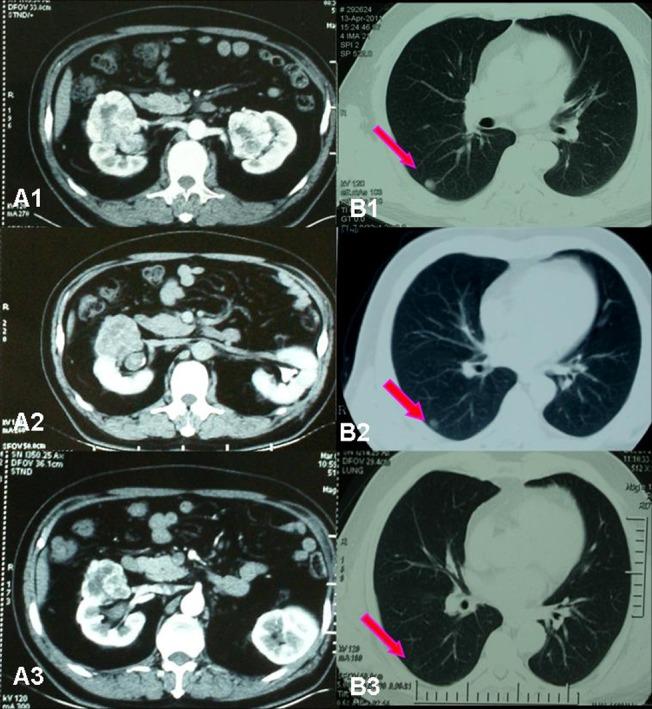

Among the 18 patients there were 13 male and 5 female, with a median age of 54.6 years. The objective response rate (ORR) of the operation on the selected patients is very high (94.4%), including 4 cases (22.2%) of partial response (PR) and 13 cases (72.2%) of stable disease (SD). After preoperative sorafenib treatment, the average tumor size of the 18 patients decreased from 7.8 cm (ranging from 3.6 to 19.2 cm) to 6.2 cm (ranging from 2.4 to 16.8 cm), and the median value of average tumor CT value decreased from 61HU to 52 HU. Among the 5 patients who had IVC tumor thrombi, the grades of tumor thrombi in 2 patients who were grade II before sorafenib treatment became grade I and grade 0 respectively, 2 patients of grade III both became grade II.

Preoperative neoadjuvant therapy with sorafenib for high risk RCC patients can significantly decrease primary tumor volume as well as tumor thrombus, which could help the nephron-sparing surgery (NSS) or radical nephrectomy to be done successfully.